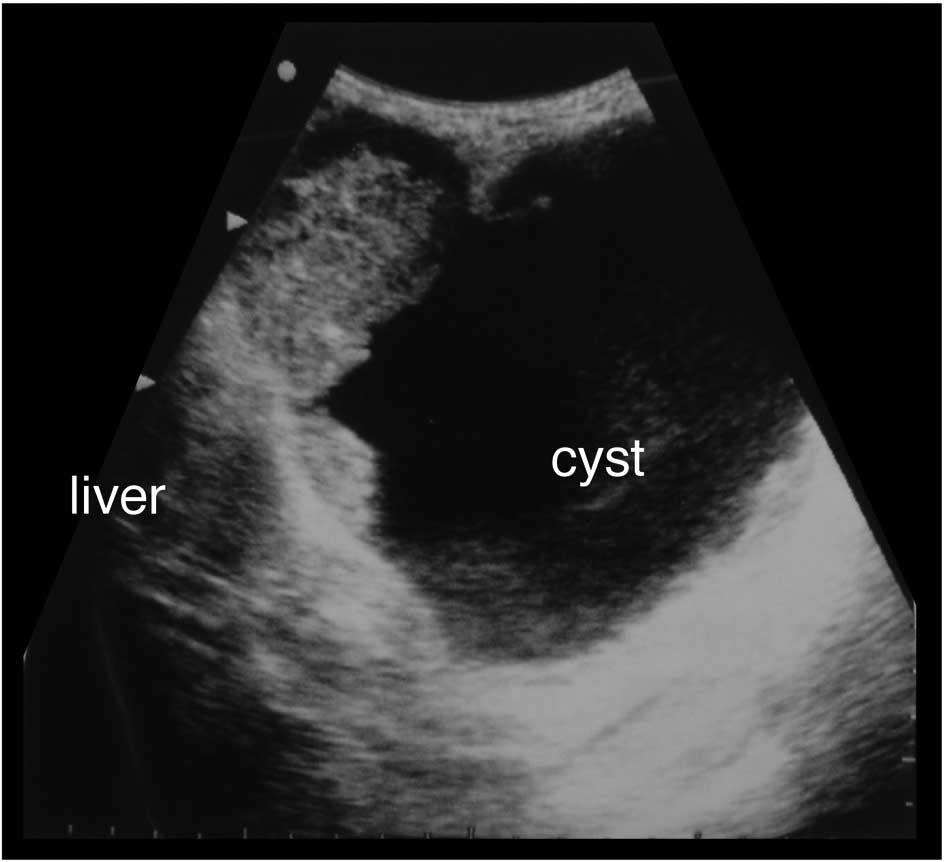

A 79-year-old Japanese female suffering from upper abdominal pain and distention was admitted to our hospital. The patient had previous illness of note nor a family history of disease. A large mass was palpable in the right upper quadrant of the abdomen. The patient’s lactate dehydrogenase was elevated to 413 IU/l (normal range <230), and two serum tumor markers, carcinoembryonic antigen (CEA) and carbohydrate antigen 19-9 (CA19-9), were both elevated at 3.4 ng/ml (normal range <2.5) and 1465.3 U/ml (normal range <37), respectively. Abdominal radiography showed an oval radio-opaque shape of 15 cm in diameter in the right upper abdomen (Fig. 1). Ultrasonography (Fig. 2) and computed tomography (CT) (Fig. 3) revealed the tumor to be a monolocular cyst with an irregular wall thickness of 15 cm in diameter concomitant with a solid mass of 8 cm in diameter around the gallbladder bed, suspected to be a tumor originating from the gallbladder. Endoscopic examinations of the alimentary tract showed no abnormalities. During celiotomy, the tumor with a large pale gray cystic component was identified at the fundus of the gallbladder. The tumor fibrously adhered to the liver, duodenum, and greater omentum, but it appeared to have only partially infiltrated into the transverse colon. A number of small nodules suspected to be tumor dissemination were scattered on the peritoneum. Gallbladder cancer with peritoneal dissemination was diagnosed. Although curative resection for the tumor was impossible, a simple cholecystectomy was performed that included the tumor without systematic lymphadenectomy, and a partial resection of the transverse colon was added due to its tight adhesion by the tumor cyst.

Figure 2

Abdominal ultrasonography showed a large cystic tumor with a solid component at the liver bed.